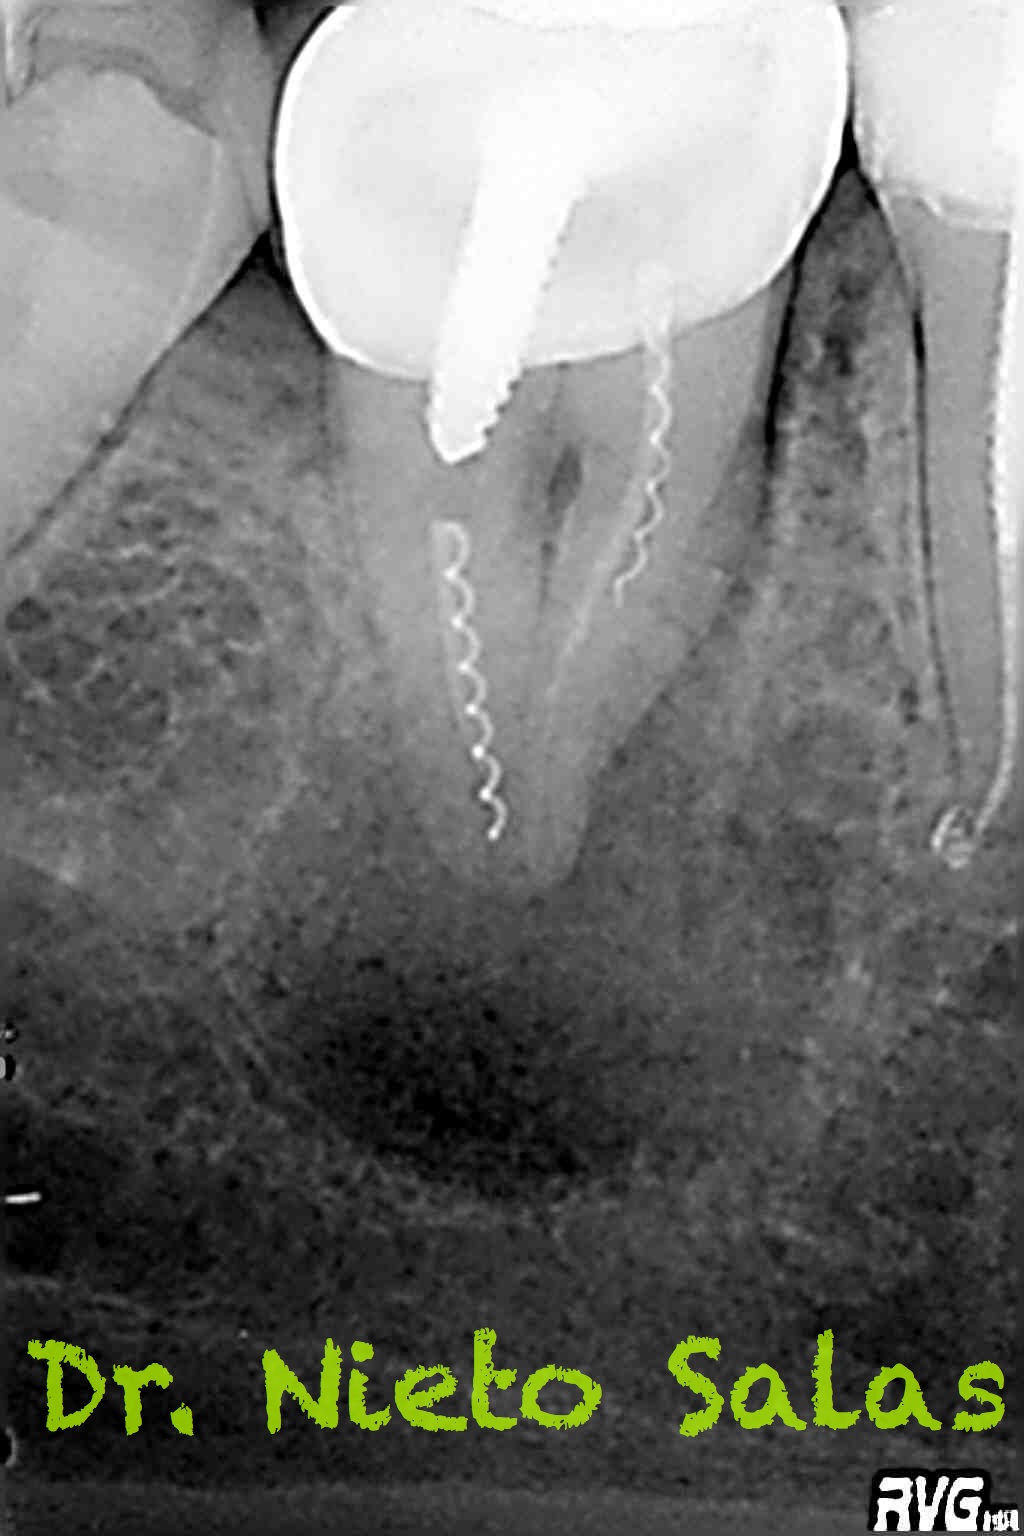

Bueno, pues nos llegó hace unos meses a revisión después de 8 meses y a la paciente se le valoraba sin síntomas y con signos evidentes de evolución positiva.